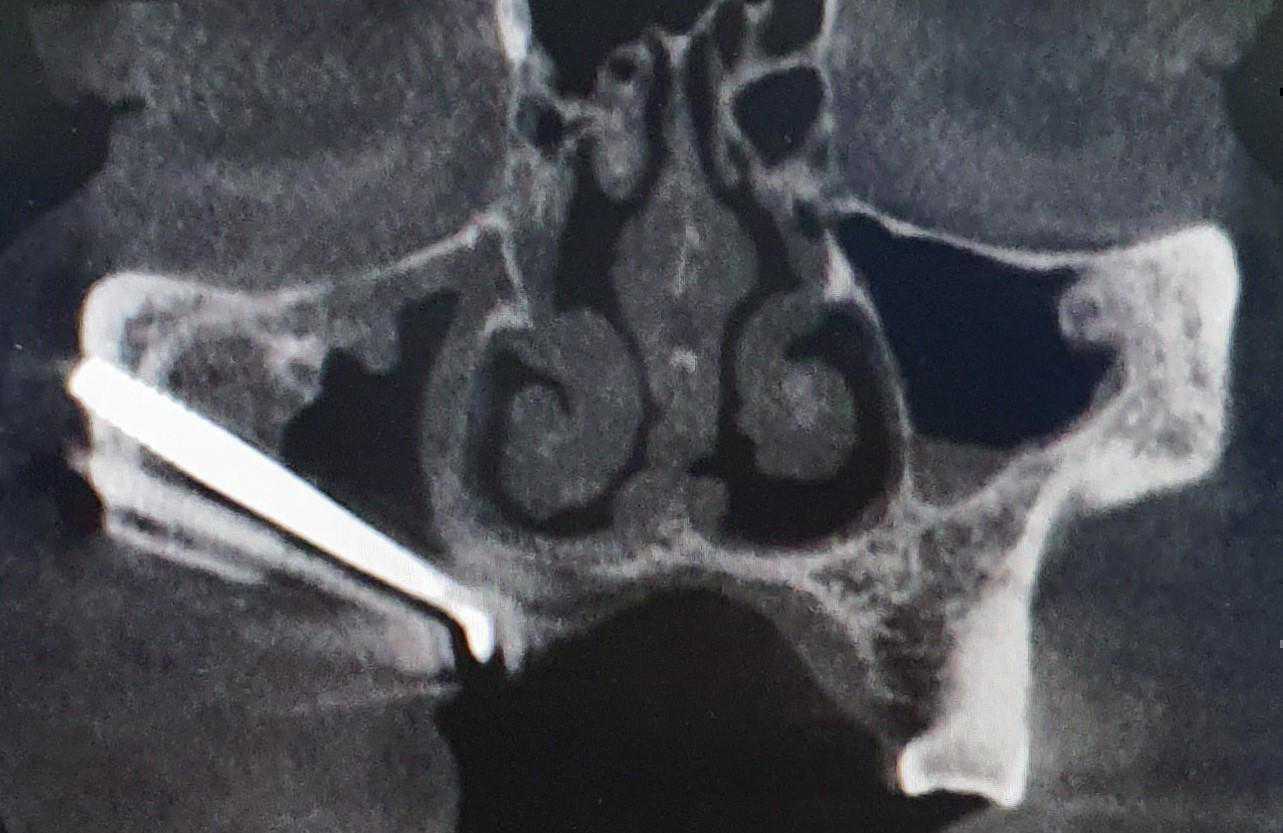

This is a case of Ameloblastic Fibro-Odontoma with a long term follow up.

https://demo.discussdentistry.com/forums/topic/should-surgery-be-done-at-13-years-of-age/#post-24451 <![CDATA[Should surgery be done at 13 years of age ?]]> https://demo.discussdentistry.com/forums/topic/should-surgery-be-done-at-13-years-of-age/#post-24451 Wed, 27 Oct 2021 08:03:10 +0000 site_admin Male patient . Age 13 years. No relevant medical history